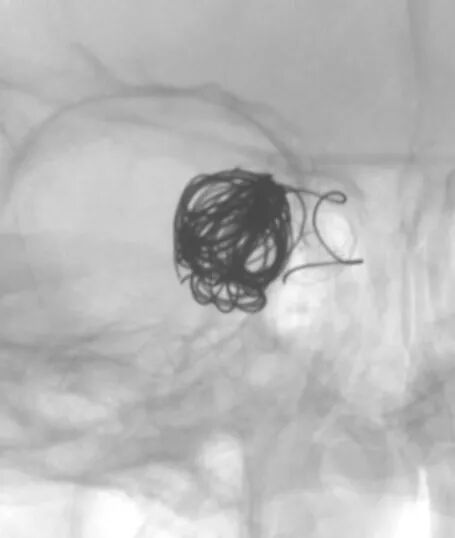

- 新路图下,沿微导管依次填入数枚弹簧圈,将动脉瘤填塞。复查造影证实动脉瘤达完全栓塞,载瘤动脉通畅。

动脉长鞘怎么置入深谋远路 | 千人皆翘首,万唤今始来——国内首款7F长鞘在血流导向密网支架联合弹簧圈栓塞治疗动脉瘤的首次应用_https://www.jmylbn.com_新闻资讯_第27张术后正位造影

动脉长鞘怎么置入深谋远路 | 千人皆翘首,万唤今始来——国内首款7F长鞘在血流导向密网支架联合弹簧圈栓塞治疗动脉瘤的首次应用_https://www.jmylbn.com_新闻资讯_第28张

术后侧位造影